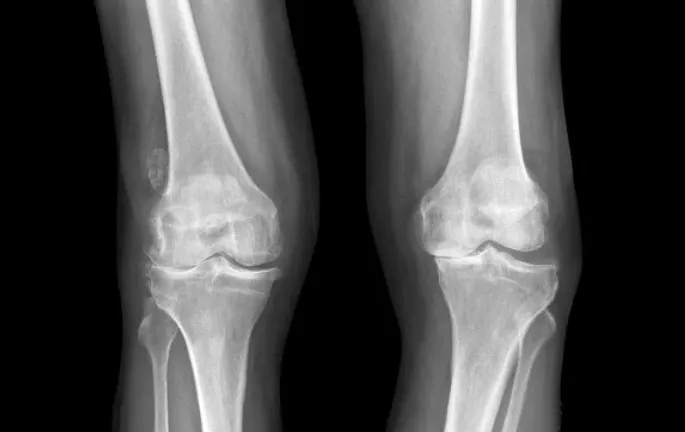

退化性關節炎是一種由於膝關節長期承受重力、外傷或免疫疾病等原因,導致關節軟骨逐漸磨損的疾病。這種情況會引發膝關節疼痛、腫脹、僵硬,甚至關節變形,嚴重影響活動能力和生活品質。由於關節軟骨的磨損是不可恢復的,因此預防和減緩磨損是一件非常重要的事情,我們將重點介紹如何透過日常保養和運動來預防退化性關節炎。

在退化性關節炎的早期階段,患者可能僅有短暫的膝關節疼痛或酸痛,休息後症狀會有所緩解。隨著病情進展,患者可能會聽到關節磨擦的喀喀聲,並感受到膝蓋不平滑的觸感。常見的症狀還包括: